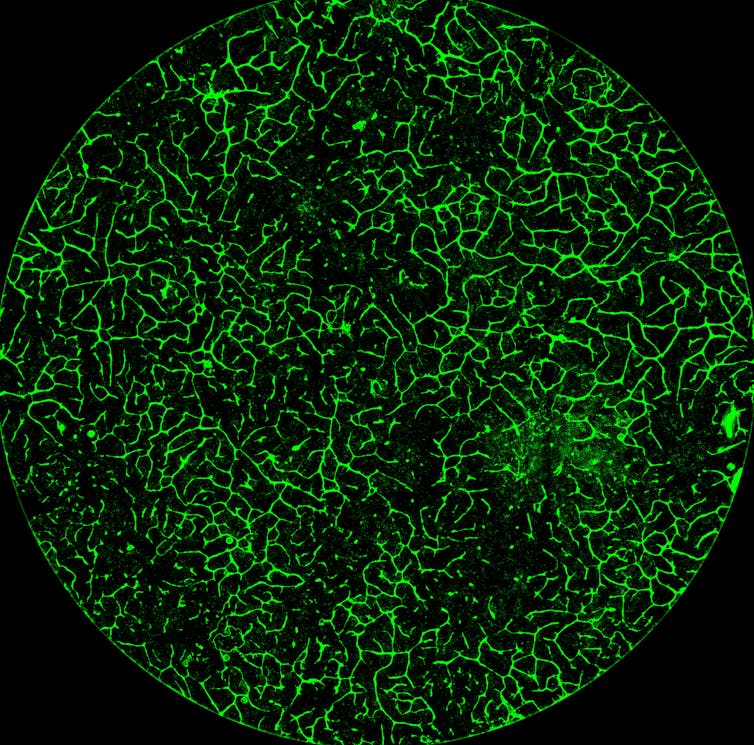

Our study demonstrates the ability of these lab livers to mature and develop a functional network of blood vessels in just two and a half weeks. We believe this approach can pave the path for the manufacture of other organs with vasculature via genetic programming.

When we implanted the lab-grown liver tissues into mice suffering from liver disease, it increased the life span. We named our organoids “designer organoids,” as they are generated via a genetic design.![]()